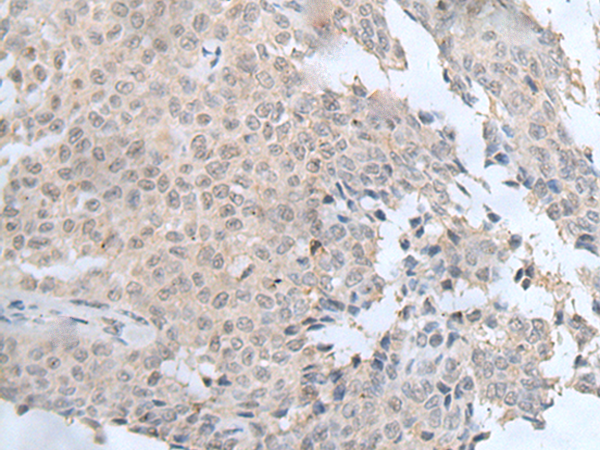

IHC positive control:

Human colorectal cancer and human ovarian cancer

IHC Recommend dilution:

20-100